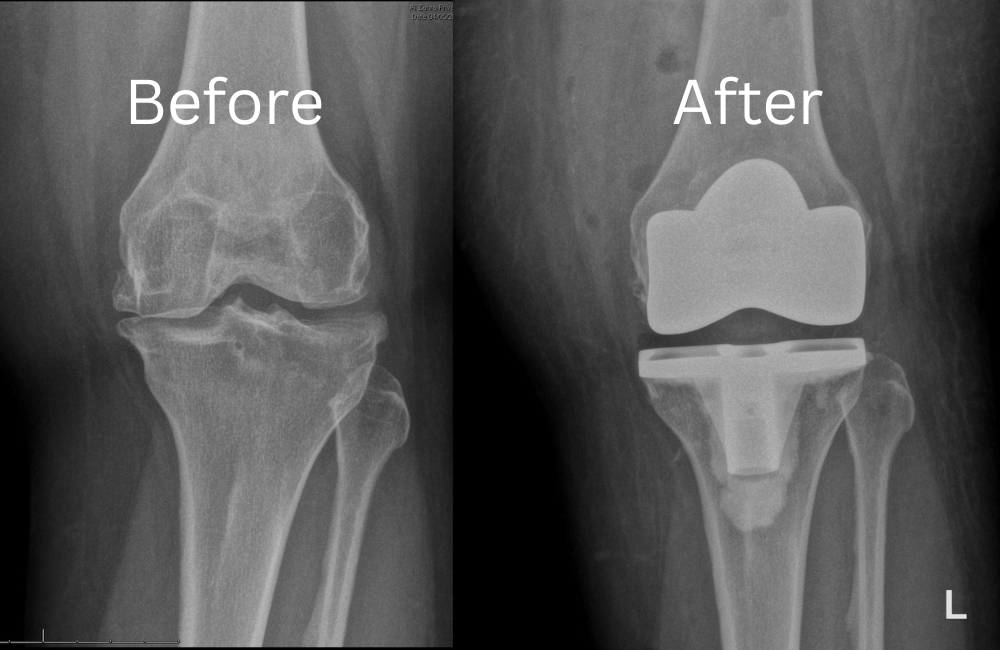

Minimally Invasive Knee Replacement is more precisely described as knee resurfacing, focuses on replacing only the worn knee joint surfaces. The procedure is performed through a small incision of approximately 10 cm (4–6 inches), significantly reducing tissue disruption and accelerating recovery. Developed and perfected by Dr. Samih Tarabichi over than two decades, the technique avoids exposure of muscles and ligaments, preserving the knee’s natural anatomy. The damaged surfaces are carefully removed with minimal thickness and replaced with advanced titanium metal components, along with a new artificial cartilage layer to restore smooth movement and eliminate pain. The incision is then closed using specialized methods designed to promote rapid healing and early mobilization. This innovative approach delivers precision, durability, and faster return to daily activities setting a new benchmark in modern knee arthroplasty.

• Prepare the bone: The damaged cartilage surfaces at the ends of the femur and tibia are removed along with a small amount of underlying bone.

• Position the metal implants: The removed cartilage and bone is replaced with metal components that recreate the surface of the joint. These metal parts may be cemented or “press-fit” into the bone.

• Insert a spacer: A medical-grade plastic spacer is inserted between the metal components to create a smooth gliding surface.